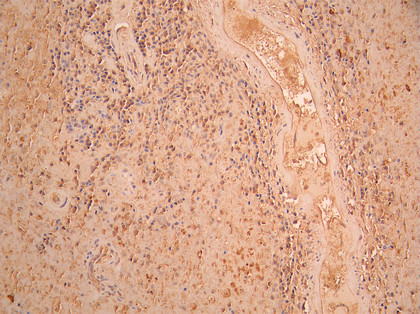

IHC image of CSB-RA945578A0HU diluted at 1:100 and staining in paraffin-embedded human pancreatic cancer performed on a Leica BondTM system. After dewaxing and hydration, antigen retrieval was mediated by high pressure in a citrate buffer (pH 6.0). Section was blocked with 10% normal goat serum 30min at RT. Then primary antibody (1% BSA) was incubated at 4°C overnight. The primary is detected by a Goat anti-rabbit polymer IgG labeled by HRP and visualized using 0.05% DAB.